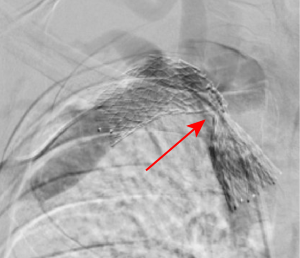

Image 2. Venous thoracic outlet syndrome with stenting at site of severe stenosis

The CT chest demonstrated “venous stent overlying the proximal right subclavian and distal right brachiocephalic vein with severe narrowing at the area of the first rib, which appears to be causing impingement of the stent.” These findings were relayed to the patient, which prompted him to recall that he had previously undergone venous stenting 3 months earlier at a nearby facility.

The patient was admitted to the medicine service, with the nephrology and vascular surgery teams following for the primary diagnosis of vascular TOS. During his hospital stay, he received HD and interventional radiology guided stenting with improvement in his right subclavian vein stenosis and a significant reduction in his RUE swelling. Vascular surgery recommended treatment with aspirin and clopidogrel and transfer to a hospital with cardiothoracic surgery capabilities for first rib resection as a definitive treatment for venous TOS.